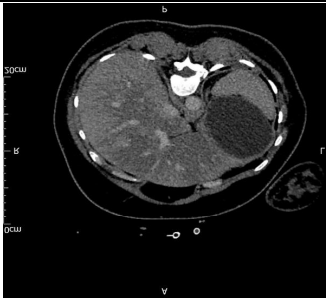

CT abdomen concluded the clinical picture of acute fatty liver in pregnancy.

Fig 1

Imaging: Ultrasound or CT may show fatty infiltration of the liver but are not definitive.

Figure 1